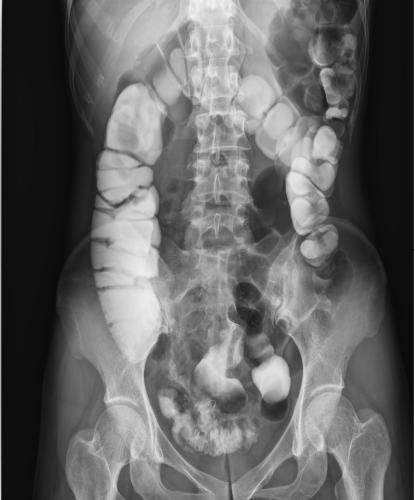

其次,數(shù)字化成像極大地提高了圖像的清晰度、對(duì)比度、分辨率,與傳統(tǒng)的胃腸機(jī)相比,空間分辨率可提高一到兩倍,圖像質(zhì)量明顯提升。還具有視頻保存回放功能,檢查結(jié)束后,仍可通過(guò)視頻回放對(duì)病人進(jìn)行診斷,不需要重復(fù)檢查。由于胃腸道疾病的癥狀大同小異,缺乏特征性,特別是一些早期無(wú)癥狀的疾病如早期胃癌或較小的病變?cè)谄渲惺芤娣藴\。動(dòng)態(tài)DRF胃腸道造影高清圖像

動(dòng)態(tài)DRF胃腸道造影高清圖像